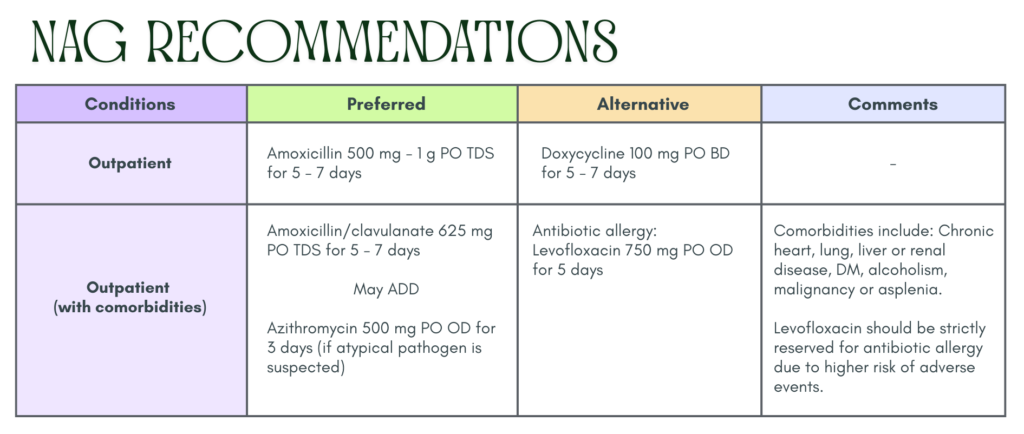

Treatment 💊

Inpatient management are not discussed here. Kindly refer to our Malaysia NAG guidelines if you would like to know more.

ATS treatment guideline

Similar to our Malaysia NAG guidelines

Outpatient (without comorbidities)

- Amoxicillin 1 g TDS or

- Doxycycline 100 mg BD or

- Macrolide (Azithromycin 500 mg D1 then 250 mg OD or clarithromycin 500 mg BD or clarithromycin extended release 1000 mg OD) monotherapy only in areas with pneumococcal resistence to macrolides < 25%

Outpatient (with comorbidities)

Augmentin 625 mg TDS or 875/125 mg BD or 2000 mg/125 mg BD or cephalosporin (cefpodoxime 200 mg BD or cefuroxime 500 mg BD)

+

Macrolide (Azithromycin 500 mg D1 then 250 mg OD or clarithromycin 500 mg BD or clarithromycin extended release

1000 mg OD)

OR

Monotherapy with respiratory fluoroquinolone (levofloxacin 750 mg OD. Moxifloxacin 400 mg OD or gemifloxacin 320 mg OD)